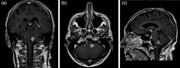

Chronic cough as a presenting feature of cerebral lymphoma

Stephen P. Williams and Mahmood F. Bhutta

Journal of Surgical Case Reports, Volume 2014, Issue 10, October 2014, rju109, https://doi.org/10.1093/jscr/rju109